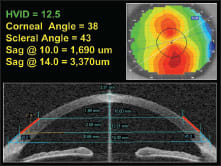

Figure 3. Corneal/scleral data, 12.5mm cornea.

As a general rule, smaller-diameter corneas exhibit less sagittal height and, conversely, larger-diameter corneas exhibit greater sagittal height (Figures 1 through 3, which profile corneas that have small, medium, and large corneal diameters). However, this is not always the case.

Topographical studies at Pacific University have shown that in normal (non-diseased) eyes, the sagittal height across a chord of 10.0mm is surprisingly consistent and contributes approximately 1,650μm to 1,750μm to the overall sagittal height. Beyond the 10.0mm chord, the eye tends to lose its curvature and forms a tangent (straight) line that extends from 10.0mm out to the limbus and sclera.